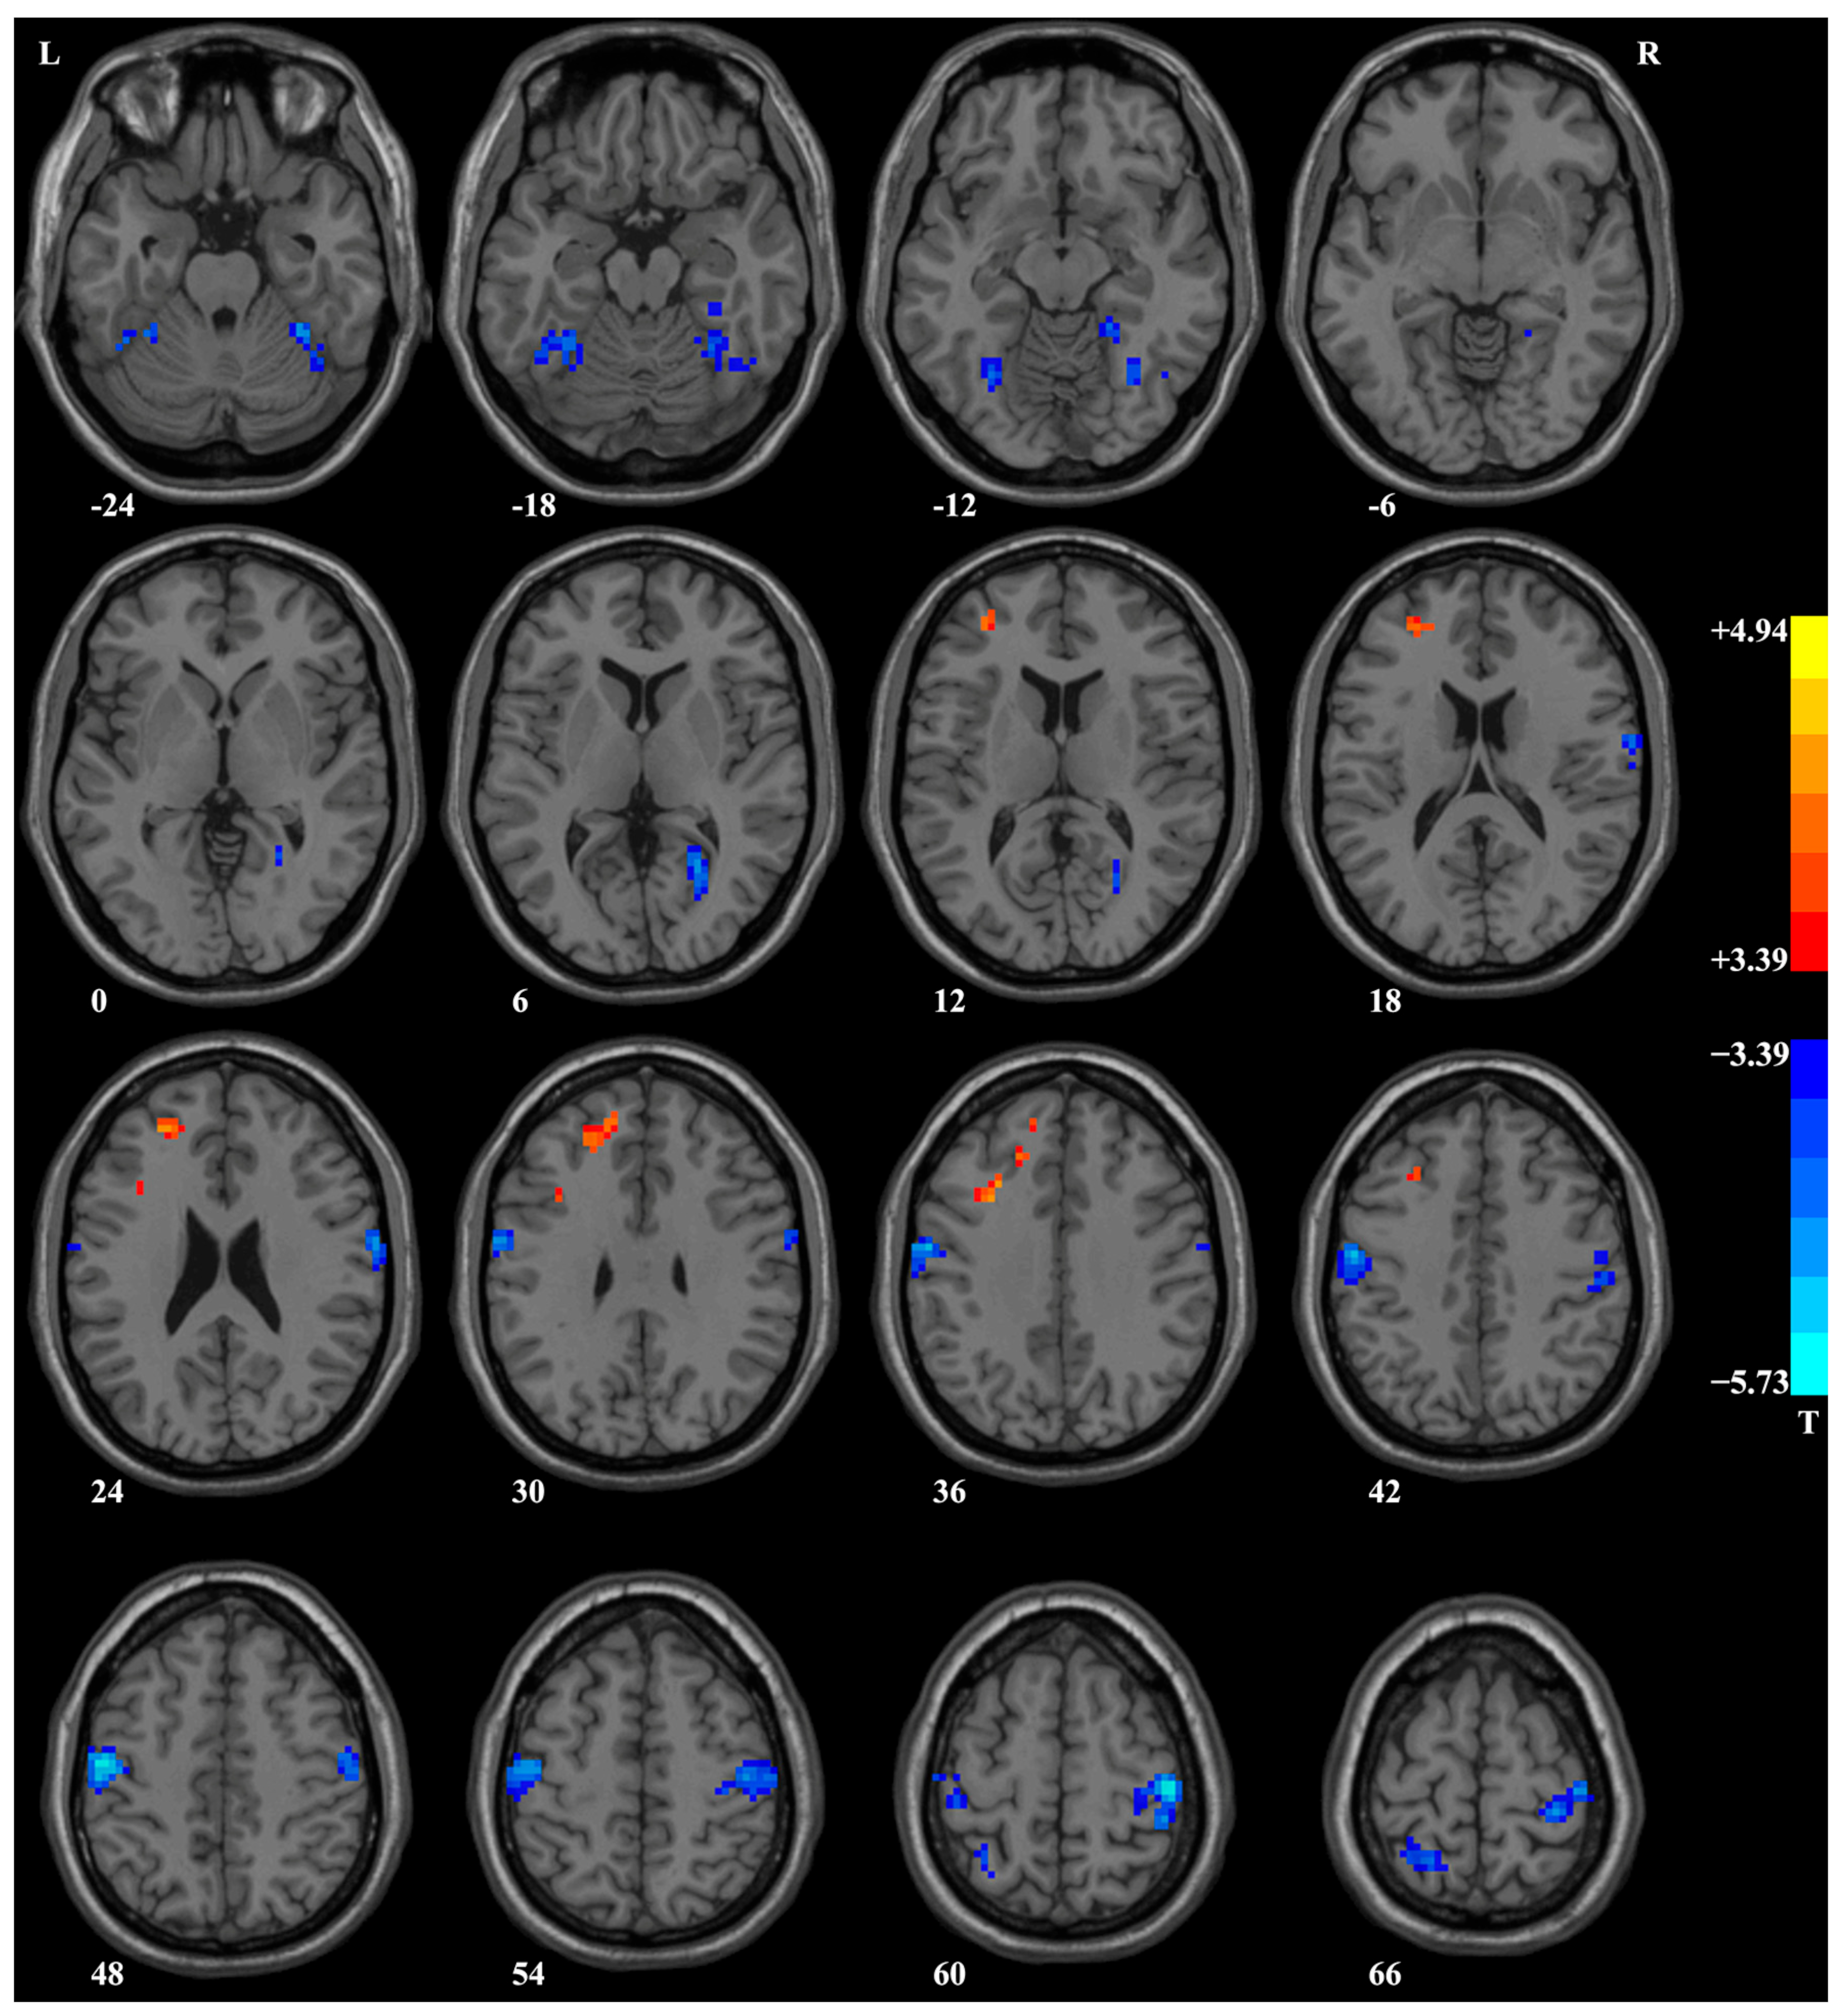

Compared to HCs, patients with PD exhibited lower ReHo in several brain regions, including the bilateral postcentral/precentral gyrus, bilateral fusiform gyrus/cerebellum VI, right calcarine/lingual gyrus, and left superior parietal lobule, and higher ReHo in the left superior/middle/inferior frontal gyrus (Table 2 and Figure 2). Significantly, after treatment, there was a notable increase in ReHo within the left fusiform gyrus in patients with PD when compared to their ReHo levels prior to treatment, as evident from the paired t-tests applied to the ReHo maps (Table 2 and Figure 3A). For further insight, ReHo values of the left fusiform gyrus were extracted from the baseline data of HCs, the baseline data of patients, the baseline data of patients who completed the follow-up, and the post-treatment data of patients. A comprehensive comparison was performed on these ReHo values using an ANOVA test (F = 10.16, p < 0.001, df = 3, r2 = 0.15) with Bonferroni-corrected post hoc t-tests (as depicted in Figure 3B). Notably, these results corroborated the findings obtained through the ReHo map comparisons.

Figure 2. Brain regions with a significant difference in ReHo between patients with PD and HCs. Compared to HCs, patients with PD showed lower ReHo in the bilateral postcentral/precentral gyrus, bilateral fusiform gyrus/cerebellum VI, right calcarine/lingual gyrus, and left superior parietal lobule and higher ReHo in the left superior/middle/inferior frontal gyrus. ReHo, regional homogeneity; PD, panic disorder; HCs, healthy controls.